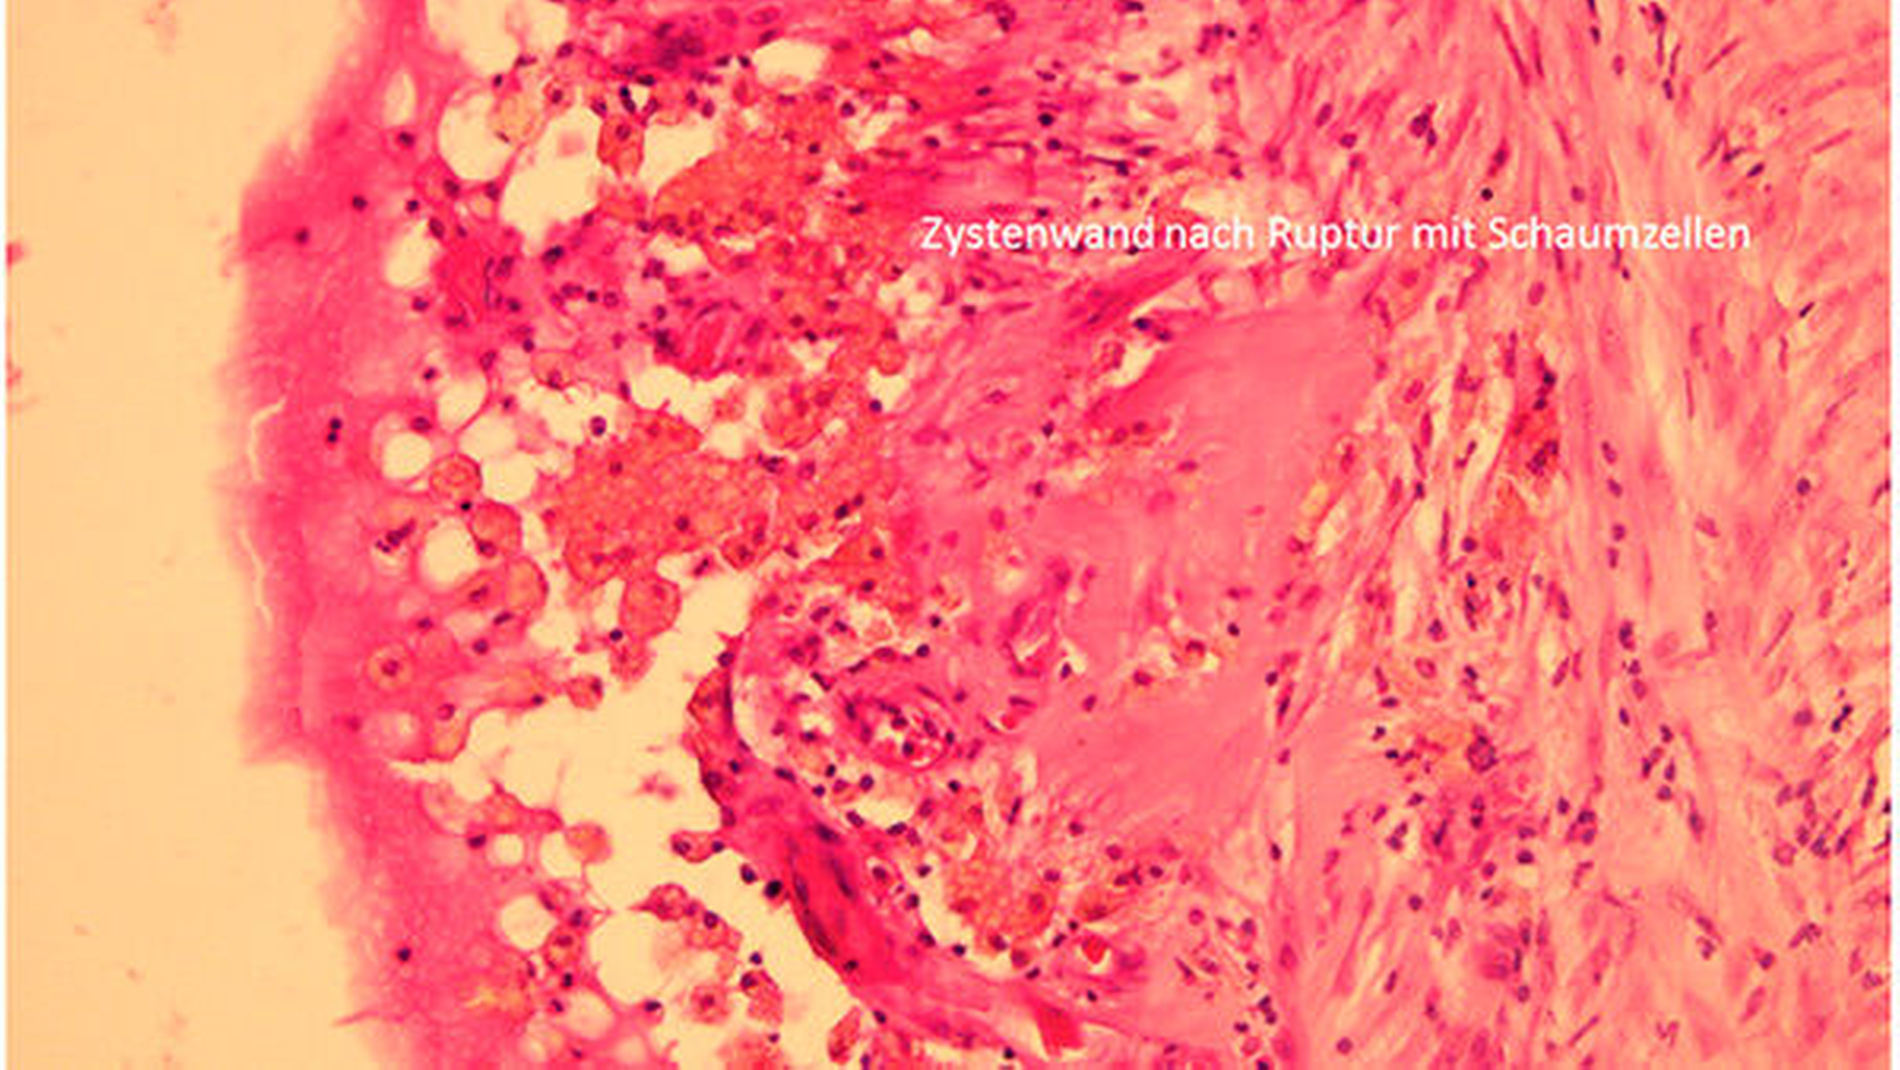

Durch die Befunde der anamnestischen, klinischen und MRT-Untersuchungen konnte die Diagnose einer medianen Halszyste gesichert werden. Die operative Entfernung der zervikalen Raumforderung wurde anschließend mit dem Patienten vereinbart und dann in Allgemeinnarkose über einen extraoralen Zugang durchgeführt (Abbildung 3a). Bei der intraoperativen Enukleation des zystisch imponierenden Gewebes konnte die Verbindung zum Os hyoideum eindeutig dargestellt werden (Abbildung 3b). Das raumfordernde Gewebe wurde dann mit dem gesamten medianen Anteil des Zungenbeins durch kontinuitätsunterbrechende Resektion entfernt (Abbildung 3c). Die feingewebliche Begutachtung des entnommenen Gewebes bestätigte in den histopathologischen Präparaten die klinisch und radiologisch gesicherte Diagnose einer medianen Halszyste (Abbildung 4).